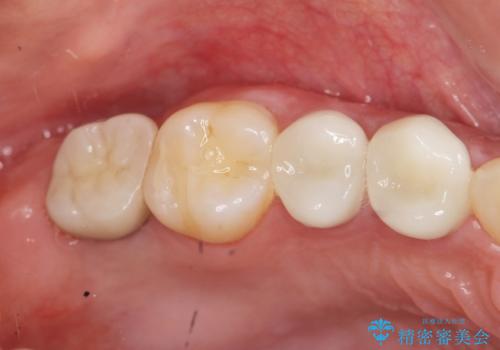

保存可能な歯の虫歯・根管治療を行い、喪失した部分はインプラントを埋入、オールセラミックジルコニアクラウンを製作し審美的に仕上げていきます。

- 120万円(仮歯×6・ファイバーコア×2・ジルコニアクラウン×6・インプラント×2・チタンカスタムアバットメント×2)費用は治療当時の料金となります